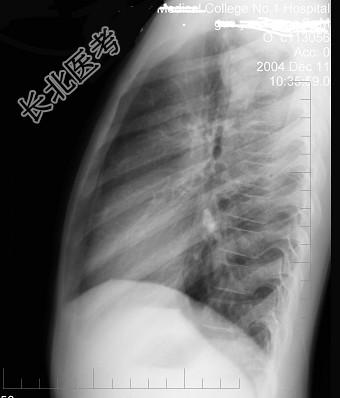

- 单项选择题男性,9岁, 常年咳嗽,无其他自觉症状, X线检查如图所示,最可能的诊断是 ( )

A、结核瘤

B、原发性肺癌

C、炎性假瘤

D、纵隔肿瘤

E、支气管扩张